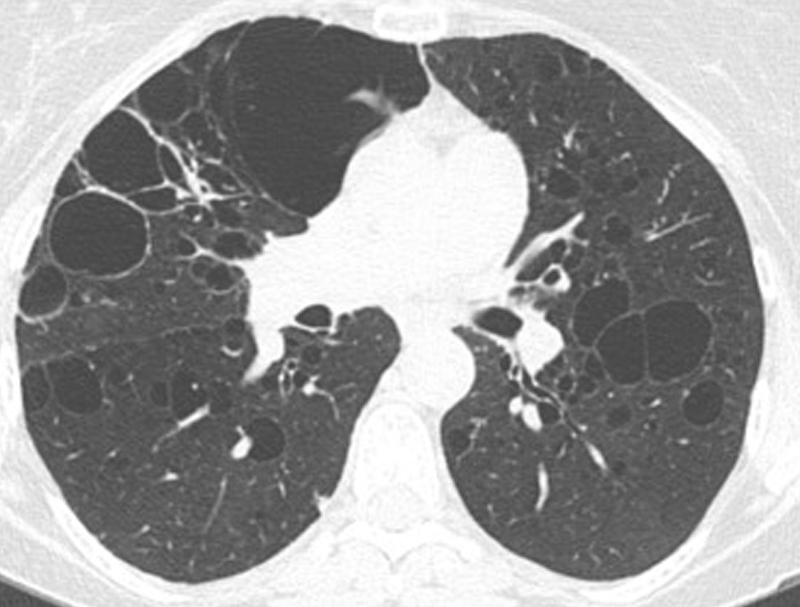

Cystic Lung Disease

Cystic Lung Disease refers to a group of lung conditions where multiple air-filled sacs (cysts) develop inside the lungs, causing breathing difficulties, recurrent infections, and reduced lung function. Early diagnosis and specialized treatment are essential to prevent long-term complications.

• High-resolution CT (HRCT) chest